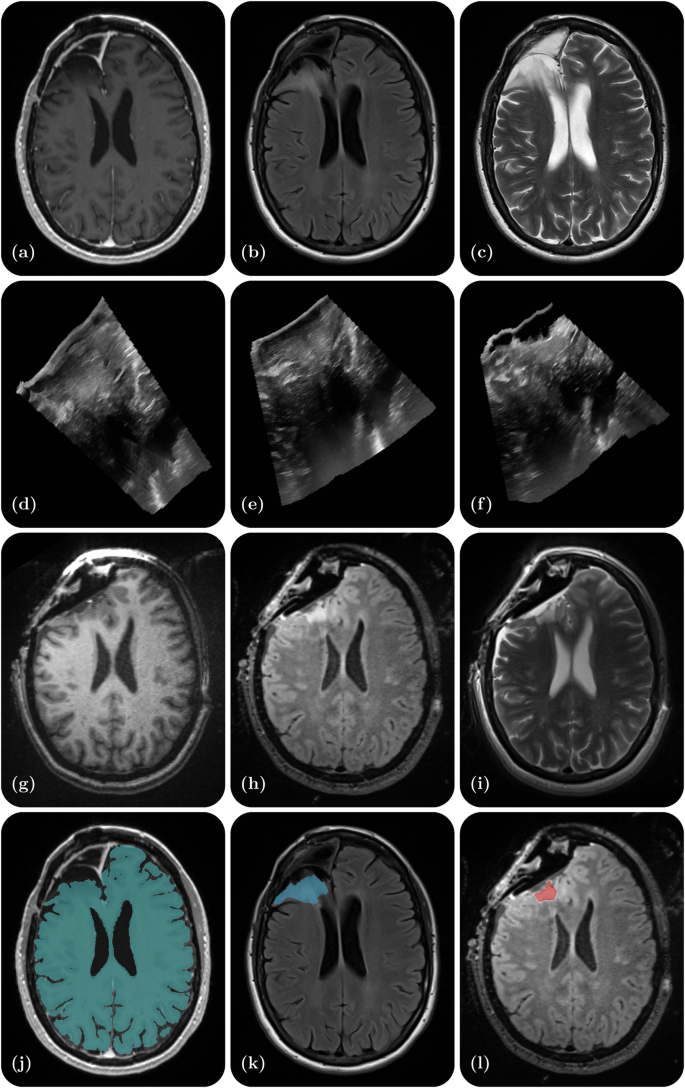

Illustrative example of one dataset - a right frontal lobe recurrent WHO Grade II Oligodendroglioma (IDH-positive, 1p/19q co-deleted). (a) Preoperative contrast-enhanced T1-weighted MR; (b) Preoperative T2-weighted MR; (c) Preoperative T2 FLAIR MR; (d) Intraoperative US prior to dural opening; (e) Intraoperative US post dural opening; (f) Intraoperative US prior to iMRI; (g) Intraoperative contrast-enhanced T1-weighted MRI; (h) Intraoperative T2 FLAIR MRI; (i) Intraoperative T2-weighted MRI (BLADE); (j) Cerebrum segmentation on the preoperative contrast-enhanced T1-weighted MRI; (k) Tumor segmentation on the preoperative T2 FLAIR MRI; (l) Residual tumor segmentation on the intraoperative T2 FLAIR MRI.

Research in the field of medical imaging and image-guided therapy is increasingly seeking large datasets to develop and test machine learning-based algorithms. Specifically, these algorithms aim at improving precision in image guided neurosurgery and interpretability by performing tasks such as image segmentation6,7 (e.g., tumor, ventricles, cerebrum, resection cavity), image registration8 (e.g., MRI-iMRI, MRI-iUS, iUS-iUS), image synthesis9 (e.g., MR to iUS and iUS to iMRI), and visualization10 (e.g., uncertainty of registration). However, sharing patient datasets for public research use is challenging due to the significant resources required for data curation as well as the need to ensure patient privacy. Moreover, datasets that combine multimodal imaging from both preoperative and intraoperative acquisitions in the same patient are particularly scarce. To address this gap, we have curated a database from neurosurgical procedures conducted in the Advanced Multimodality Image Guided Operating (AMIGO) suite at the Brigham and Women’s Hospital. This database represents the largest publicly-available collection of preoperative MRI, intraoperative MRI, and intraoperative ultrasound data from surgically treated brain tumors. It contains 92 gliomas, 11 metastases, and 11 non-glioma pathologies. The database includes 369 preoperative MRI series, 320 three-dimensional iUS sweeps, 301 iMRI series, and 356 segmentations obtained from 114 consecutive patients who underwent image-guided resection at a single institution. Additionally, each case contains segmentations of the preoperative tumor, the pre-resection cerebrum, and the previous resection cavity derived from the preoperative MRI (if applicable), as well as any residual tumor identified on the iMRI. For reference, Fig. 1 provides an illustrative example of the contents of each dataset and all available segmentations.